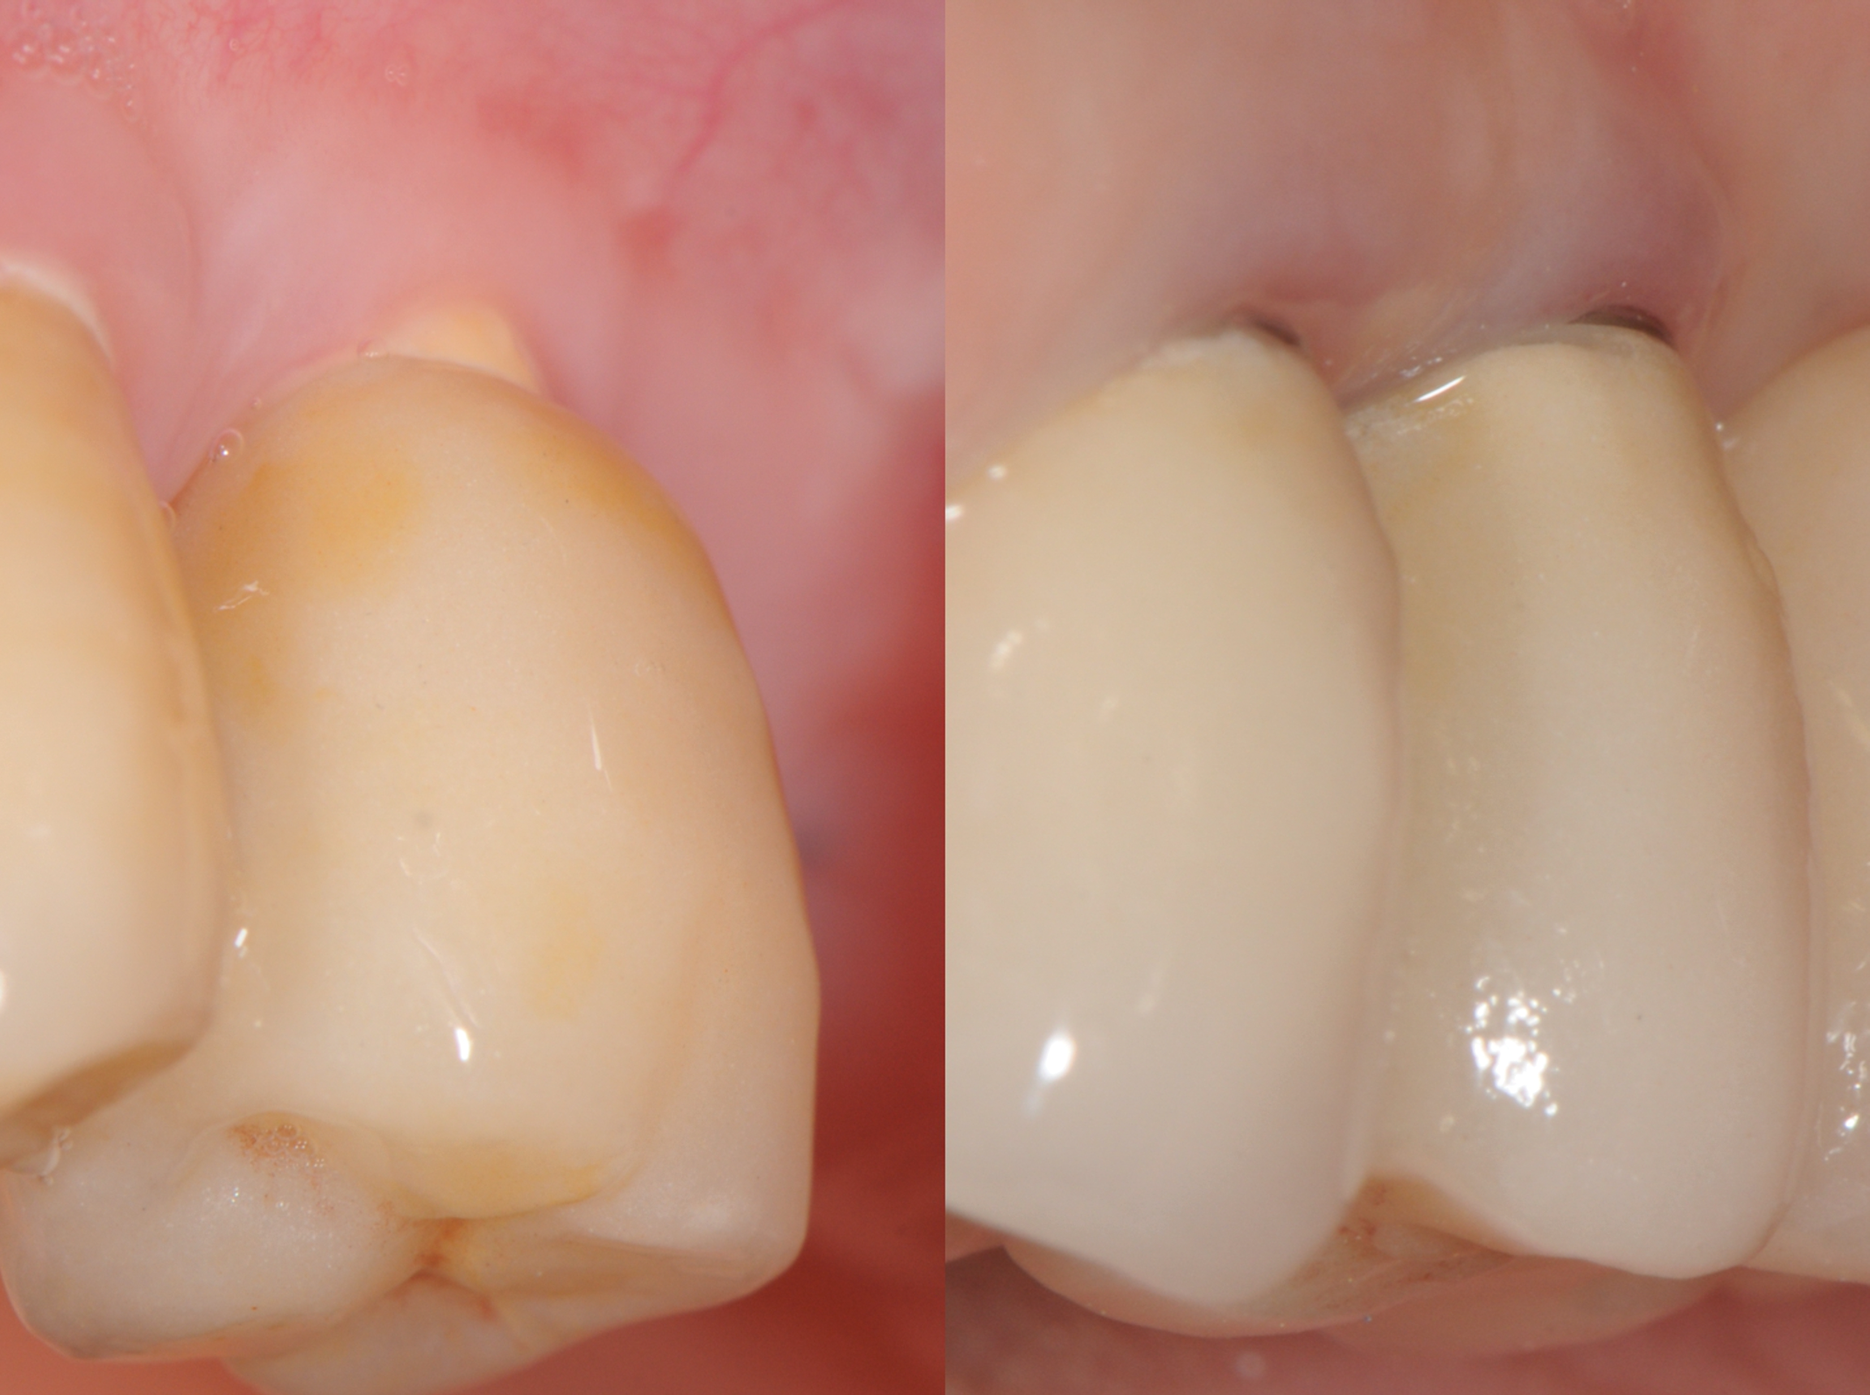

Still, as with titanium implants, undesirable recession with an exposed implant shoulder may occur in rare cases with ceramic implants. Nonetheless, from an esthetic point of view, this inflammation-free recession of the gingiva is likely to be tolerated much better by patients concerned with the dark margins of titanium implants (Figure 2).

Fig 2. Recessions in ceramic (left) and titanium (right) implants.

Figure 2